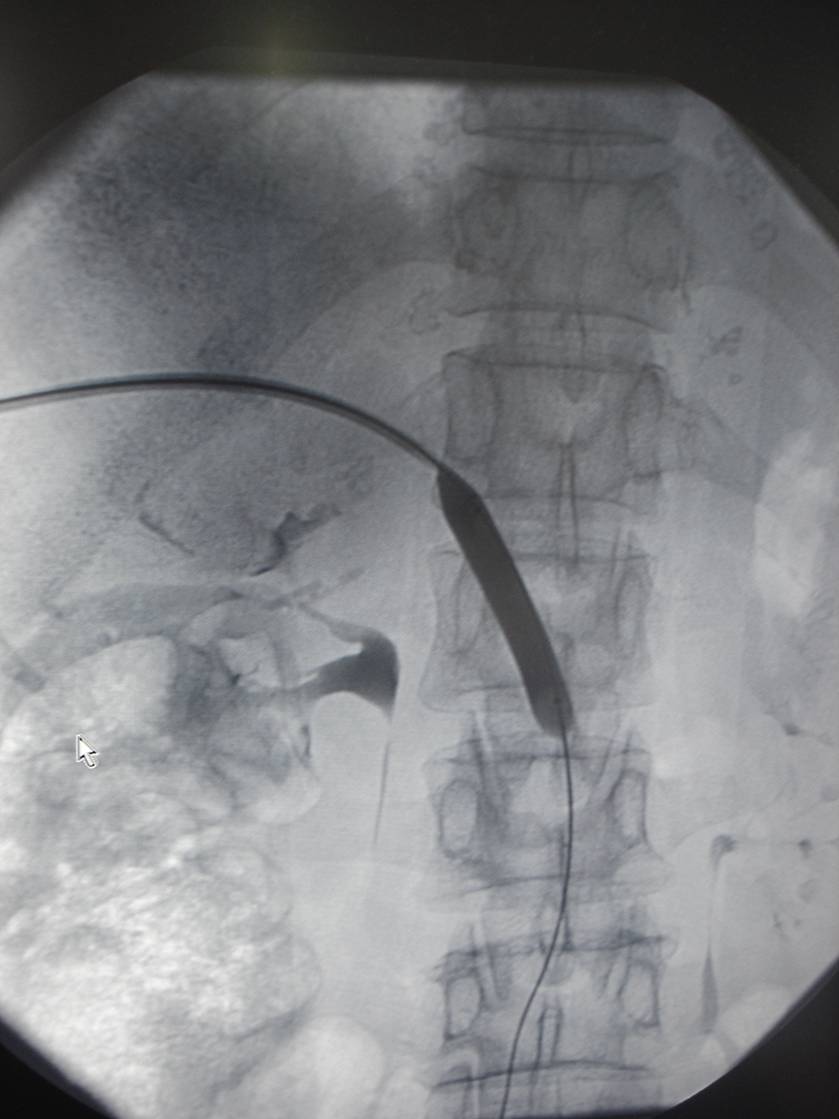

经全科讨论并请普外科、介入科会诊后,考虑慢性胰腺炎所致门静脉狭窄、区域性门脉高压,周围迂曲的侧枝循环导致胆肠吻合口处多发血管扩张并出血。患者转入介入科门静脉造影见门脉远端重度狭窄,用球囊扩张狭窄段,并自肠系膜上静脉及门静脉植入支架。